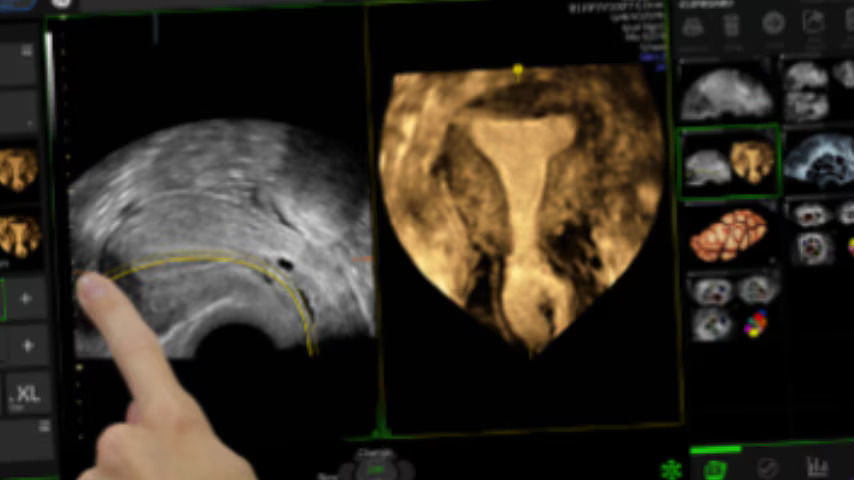

Sonopelvicfloor

Assess pelvic floor anatomy using guided workflow & AI

Using a guided workflow and AI, SonoPelvicFloor:

• removed exam complexity by automating plane alignment and measurements

• can reduce keystrokes by up to 75% and offer users a time savings of up to 80%